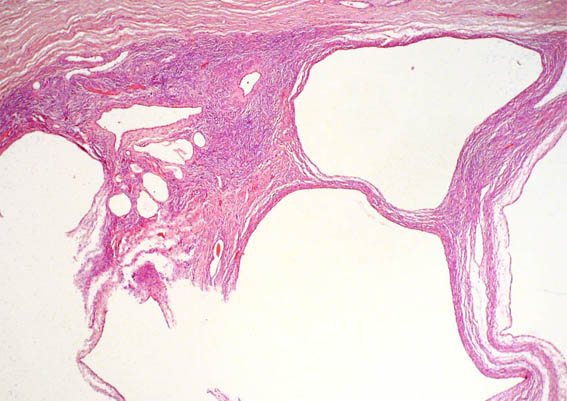

A 36-year-old woman presented with left flank pain for 2 months. She denied fever, gross hematuria, or body weight loss. Ultrasonography revealed a multicystic mass with multiple septa in the left kidney. Nephrectomy was done.

Figure 3. H&E, X100.